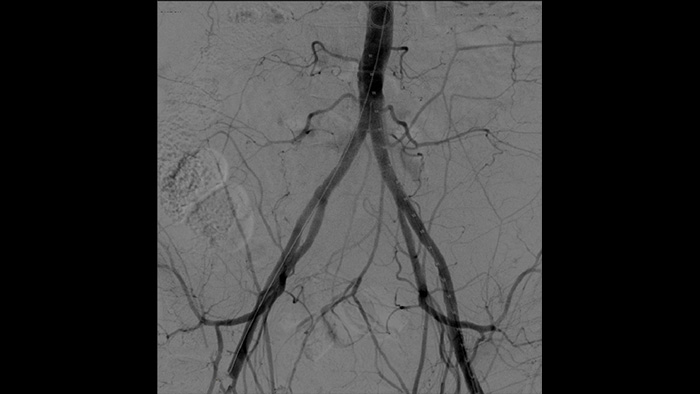

La angiografía por sustracción digital (DSA) se utiliza en procedimientos vasculares intervencionistas para visualizar claramente los vasos sanguíneos mediante la eliminación de estructuras que puedan oscurecer la visibilidad de los vasos. La fluoroscopia Roadmap superpone una imagen de contraste sustraída previamente adquirida en la fluoroscopia en tiempo real, lo que le permite rastrear un dispositivo sin volver a inyectar el contraste.

Uno de los principales especialistas de España en cirugía vascular mínimamente invasiva es el Dr. Ramon Vila, jefe del Departamento de Angiología y Cirugía Vascular, Hospital Universitario de Bellvitge, Barcelona, España. Este hospital realiza 1000 cirugías vasculares al año. Con el arco de quirófano Zenition de Philips, el Dr. Vila obtiene excelentes imágenes de alta calidad que le permiten realizar la mayoría de los procedimientos vasculares en la configuración de dosis baja.

Con Zenition, nuestra calidad de imagen DSA ha mejorado mucho. Ya no vemos una imagen granulada, sino una imagen muy clara."